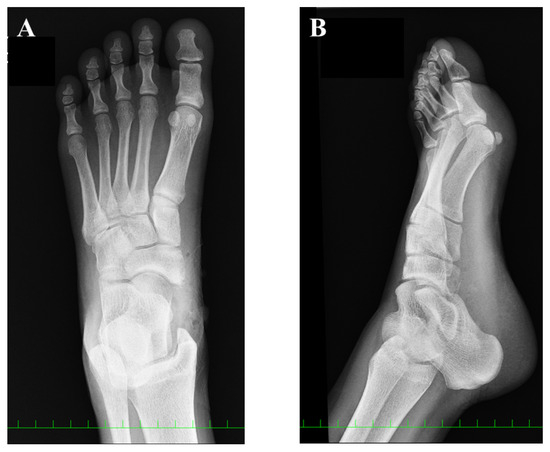

2. Case Presentation